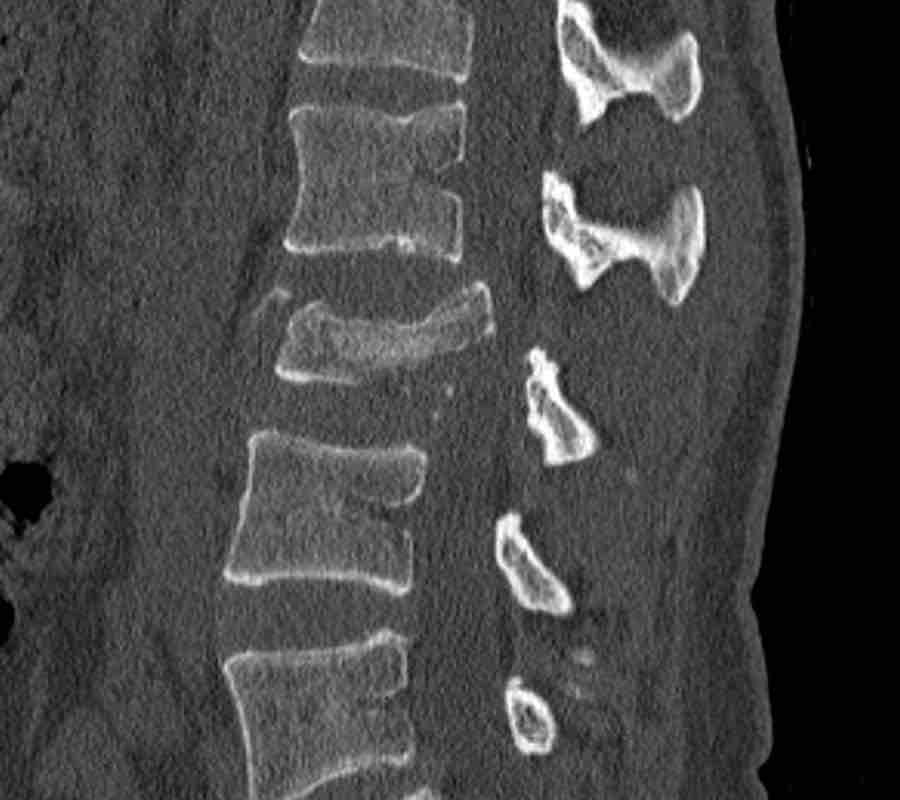

Findings:

- No C or B injury

- Fractures vertebral body with involvement of upper endplate (1 point) and posterior wall (2 points)

Conclusion

Injury type A3